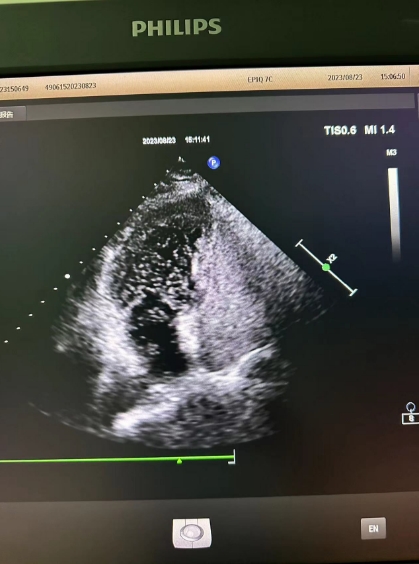

超聲心動(dòng)圖檢查發(fā)現(xiàn)可能存在卵圓孔未閉,經(jīng)心內(nèi)科會(huì)診,詳細(xì)詢(xún)問(wèn)病情、仔細(xì)了解病史后,為進(jìn)一步明確診治,決定為患者進(jìn)行右心聲學(xué)造影檢查。右心聲學(xué)造影是一項(xiàng)無(wú)創(chuàng)、便捷的超聲檢查技術(shù),醫(yī)護(hù)人員首先在患者胳臂上建立一個(gè)靜脈通路,然后把含有微小氣泡的振蕩生理鹽水注入患者體內(nèi),同時(shí)將超聲探頭放在患者心前區(qū),借助超聲檢查設(shè)備,觀察進(jìn)入人體心腔的微小氣泡運(yùn)動(dòng)情況。

患者檢查后果然發(fā)現(xiàn)了異常,從屏幕上可以清晰看到,患者左心房?jī)?nèi)很快出現(xiàn)了大量微小氣泡,這說(shuō)明該患者的心臟存在著房水平由右向左的分流,提示有先天性卵圓孔未閉!根據(jù)這一檢查結(jié)果與患者及家屬溝通后,心內(nèi)科為其進(jìn)行了卵圓孔未閉封堵術(shù),最終改善了患者多年來(lái)的頭暈頭痛癥狀。